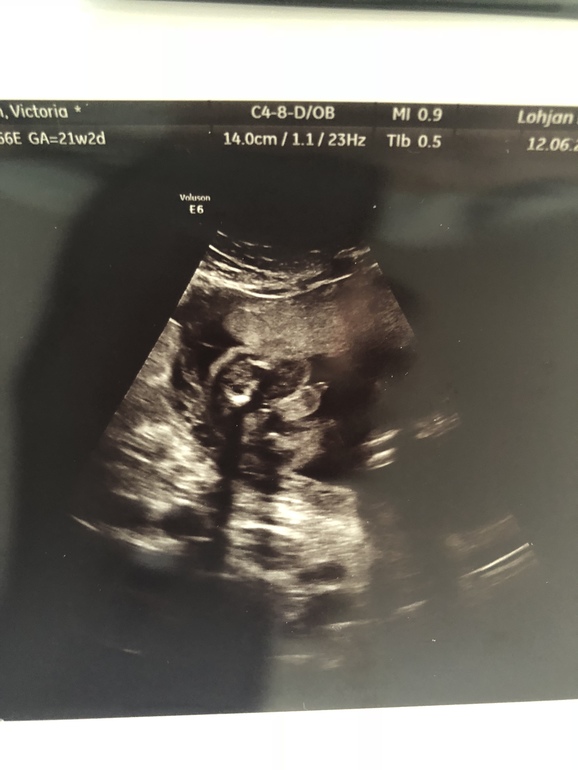

Срок 21+2 все в полном порядке, все соответствует сроку:) вес 396гр. И мальчика нам подтвердили🙈😍💙💙💙 люлька с синим капюшоном уже дома , одежду начала покупать , я в счастливом шоке! Также не может н

радовать что я худею потихоньку , добеременности 95,7 сейчас 90,7:) хочу ещё :) Ну и фоточек несколько , т к плацента по передней стенке Было очень трудно сфотать